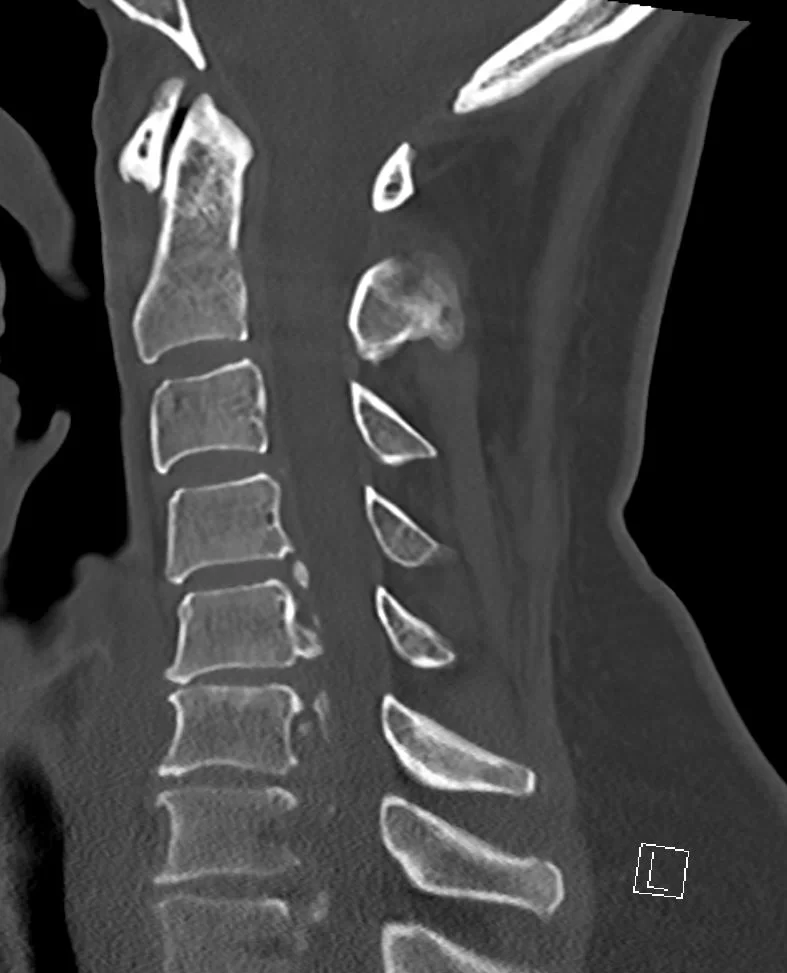

Ο απεικονιστικός έλεγχος έλεγχος με μαγνητική και αξονική τομογραφία της αυχενικής μοίρας της σπονδυλικής στήλης ανέδειξε σημαντική εκφύλιση της αυχενικής μοίρας της σπονδυλικής στήλης με πολυεπίπεδη στένωση λόγω εκτεταμένης οστεφύτωσης και επασβέστωσης του οπισθίου επιμήκους συνδέσμου.

Διενεργήθη σωματεκτομή του Α6 σπονδύλου και δισκεκτομή Α7/Θ1 καθώς και τοποθέτηση πλάκας Α5-Θ1.

Σ’ αυτήν την περίπτωση εφαρμόσαμε το συνδυασμό δύο τεχνικών: της σωματεκτομής για τον Α6 σπόνδυλο (προκειμένω να αποσυμπιέσουμε τα επίπεδα Α5/6 και Α6/7 αλλά και να αποκαταστήσουμε τη φυσιολογική λόρδωση της αυχενικής μοίρας της σπονδυλικής στήλης) και της δισκεκτομής στο επίπεδο Α7/Θ1. Αυτό μας επέτρεψε να αποσυμπίεσουμε και στα 3 επίπεδα στα οποία υπήρχε η σημαντικότερη στένωση, αλλά ταυτόχρονα αποφύγαμε μια πιο εκτεταμένη σωματεκτομή η οποία ενδεχομένως να μας ανάγκαζε να προβούμε σε συμπληρωματική οπίσθια σπονδυλοδεσία.